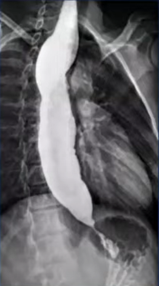

Q186. A 32-year-old male presents with dysphagia and regurgitation. A barium swallow image is shown. Which investigation is considered the gold standard for confirming the diagnosis?

- CECT

- Esophageal manometry

- Endoscopy

- NCCT

Answer: B